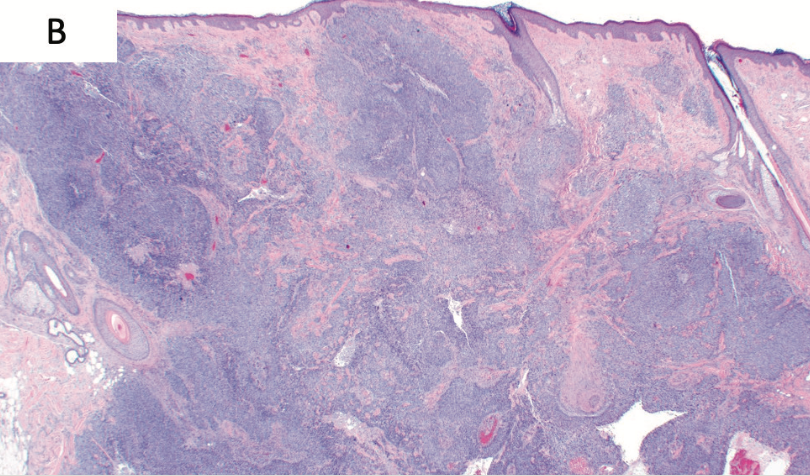

A man, aged 56 years, originally presented to dermatology with a 26-mm erythematous, markedly exophytic tumor on the vertex scalp with 2 adjacent satellite lesions (Figure 1). Biopsies were obtained from both the main and adjacent lesions. Microscopic examination of the main mass revealed a nodular aggregate of peripherally palisaded basaloid cells as well as infiltrating cords set in fibromyxoid stroma with a second population of atypical spindle cells (Figure 2A). These 2 cell populations were intimately intertwined. Immunostains including CD10, CD34, and S100 were negative throughout, speaking against a primary cutaneous sarcoma (including dermatofibrosarcoma protuberans and pleomorphic undifferentiated sarcoma). Ber-EP4, pancytokeratin, and p63 were negative in the spindle cell population, but positive within the basaloid component (Figure 2B). This primary tumor was classified as a carcinosarcoma with features of a spindle cell sarcoma and BCC. The adjacent satellite lesions displayed nests of basaloid keratinocytes with peripheral palisading and retraction artifact, which was compatible with a diagnosis of BCC. At the time, the vertex scalp lesion and adjacent nodules were deemed to represent separate primary tumors (Figure 2C). All lesions were treated by Mohs micrographic surgery. Radiation was offered as adjuvant therapy for the main mass, but the patient declined and was subsequently lost to follow-up.

FIGURE 2. Histopathologic Features of Original Tumors